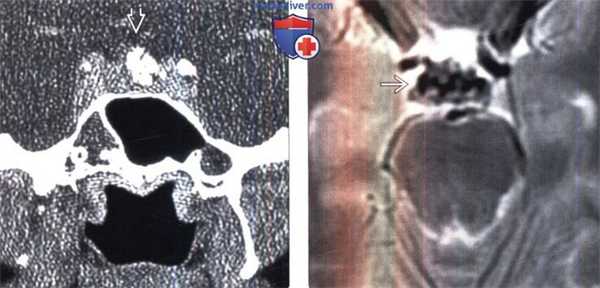

(Слева) Бесконтрастная КТ, аксиальный срез: расширение левых отделов средней черепной ямки в сочетании с истончением вышележащего свода черепа за счет слегка гиперденсного объемного образования с четкими контурами. Объемное образование практически полностью заполняет среднюю черепную ямку, распространяясь в заднюю черепную ямку и в турецкое седло/пещеристый синус.

(Справа) КТ, костное окно, аксиальный срез: у этого же пациента определяется расширение левых отделов средней черепной ямки и экстенсивное истончение вышележащего свода черепа.Также наблюдается ремоделирование костного компонента турецкого седла. (Слева) МРТ, Т2-ВИ, аксиальный срез: у этого же пациента объемное образование имеет выражено гиперинтенсивный сигнал В и практически полностью заполняет левые отделы средней черепной ямки, распространяясь в заднюю черепную ямку и в турецкое седло/пещеристый синус.

(Справа) МРТ, постконтрастное Т1-ВИ, режим подавления сигнала от жира, аксиальный срез (этот же пациент): интенсивное однородное контрастное усиление объемного образования. При операции была обнаружена гемангиома пещеристого синуса. Гемангиома должна быть включена в дифференциально-диагностический ряд интенсивно накапливающих контраст объемных образований пещеристого синуса, выглядящих практически полностью экстрадуральными.